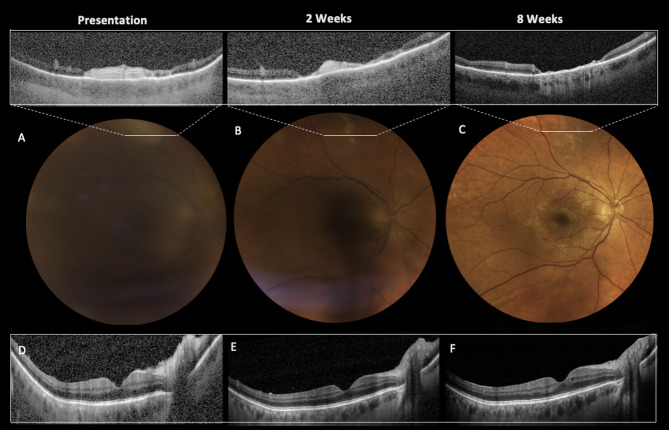

Unilateral uveitis following adjuvanted Varicella-Zoster subunit vaccine in a patient with previously resolved Varicella Zoster acute retinal necrosis.